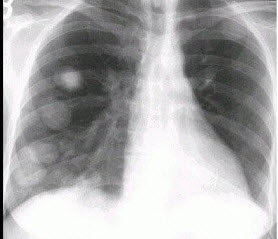

60、单项选择题

男,45岁,HBV阳性10年,胸痛1月余伴咳嗽,咯血1天,胸片如图,最可能的诊断是()

A.肺多发性脓肿

B.肺韦格肉芽肿

C.HBV病毒肺部转移

D.金葡菌感染

E.肺转移瘤